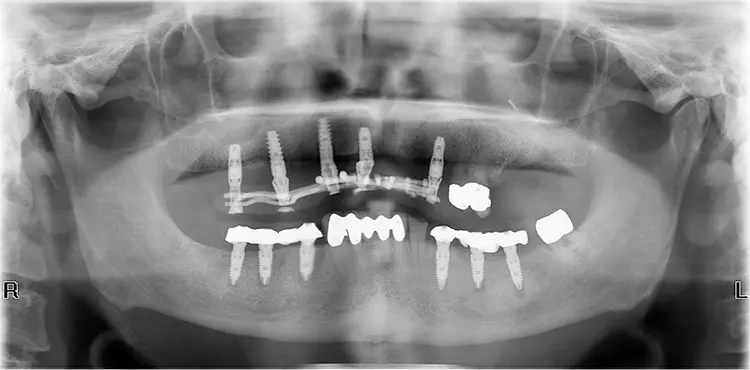

Für das Umsetzen unter Berücksichtigung der genannten Ziele im klinischen Alltag stellen wir einen exemplarischen Behandlungsfall vor. Bei dem 71-jährigen Patienten gilt es, die 2 entstandenen Unterkieferseitenzahnlücken bei guten knöchernen Voraussetzungen implantologisch zu versorgen (Abb. 2 und 3).

Der Patient ist Nichtraucher mit unauffälliger allgemeinmedizinischer Anamnese. Der Oberkiefer ist bereits seit vielen Jahren mit Implantaten und einem festsitzenden WeldOne Schweißgerüst (Dentsply Sirona) versorgt und bildet ein sicheres antagonistisches Widerlager für die geplante Unterkieferarbeit.

Anschließend wird ebenfalls im Labor die bereits vorliegende Keramikschalenverblendung auf das Gerüst endgültig verklebt und insbesondere basal ausgearbeitet und poliert. Da dies nicht viel Zeit in Anspruch nimmt, kann in der gleichen Sitzung die keramikverblendete finale Rehabilitation bei sehr guter Prognose endgültig eingesetzt werden (Abb. 13 und 14).